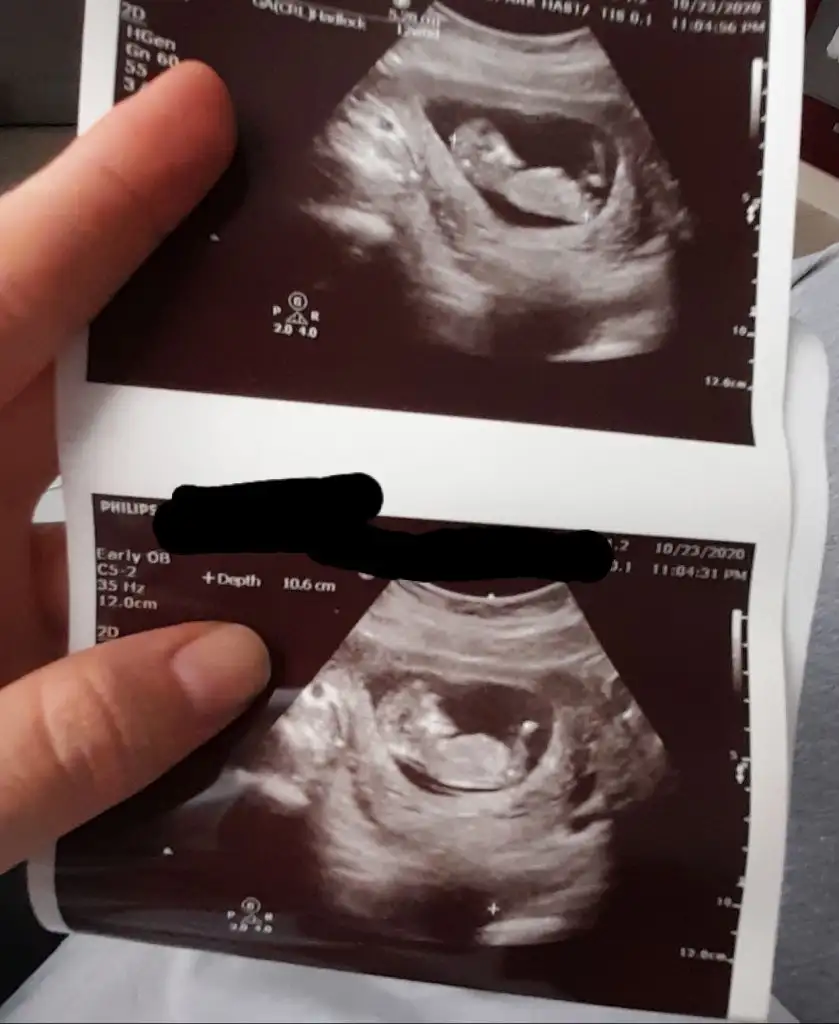

11haftaya girdikte doktor net göremedi. Yiyip içmiyorsun heralde dedi usg net gözükmedi. 16.sında tekrar gidicem inşallahSanki küçük 11 12 13 haftalar olmalı

Kız gibiEki Görüntüle 2717986 merhaba yorumlayabilirmisiniz acaba

Seninkisi erkek canımEki Görüntüle 2717986 merhaba yorumlayabilirmisiniz acaba